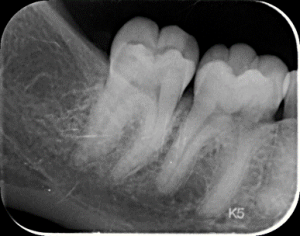

La carie dentaire est comme une pomme qui commence à se détériorer à sa surface. Elle est causée par des bactéries présentes dans la plaque dentaire, qui produisent des acides. Sans traitement, cette détérioration peut s’étendre à travers la dent et atteindre la pulpe sous-jacente, entraînant des douleurs et des problèmes plus graves infectieux.

Un abcès dentaire est une infection bactérienne douloureuse qui se forme au niveau de la racine d’une dent ou entre la dent et la gencive. Cela peut survenir lorsque la carie dentaire n’est pas traitée, permettant aux bactéries d’atteindre la pulpe dentaire, où se trouvent les nerfs et les vaisseaux sanguins. L’abcès se développe lorsque le corps réagit à l’infection en envoyant des globules blancs pour combattre les bactéries, créant ainsi une accumulation de pus.